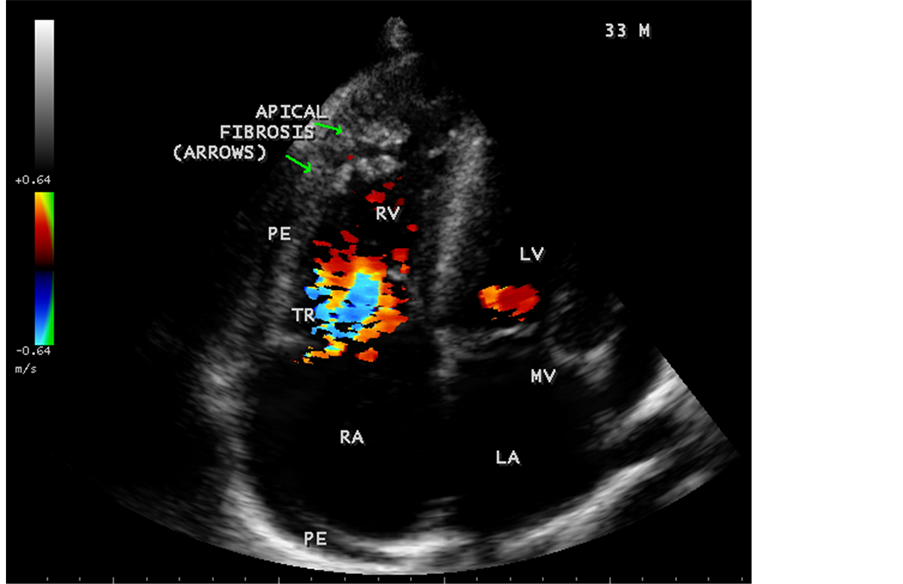

Figure 30. Showing thick fibrous strands in the right ventricle with mild pericardial effusion suggesting right ventricular endomyocardial fibrosis in a 33-year-old male.

Figure 31. Showing tricuspid regurgitation with thick fibrous strands in the Right ventricle in a 33-year-old male in RV EMF.